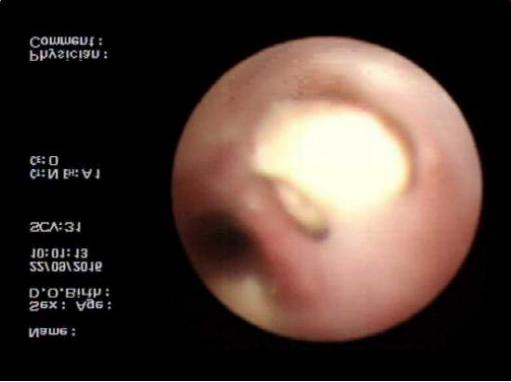

病例1: 巩先生,体检发现左肺毛玻璃小结节,用EBUS-GS超声支气管镜进行检查,病理结果:隐球菌感染。